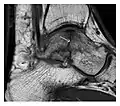

a

b

Figure 7: Fatigue fracture of the talus in a 25-year-old male basketball player with right hind foot and ankle pain, without history of trauma, and a normal initial radiograph (not shown). (a) One-month followup lateral radiograph shows normal appearance. (b) Sagittal T1-weighted MRI shows an irregular fracture line (arrow) within an ill-defined area of hypointensity corresponding to bone marrow edema.[1]